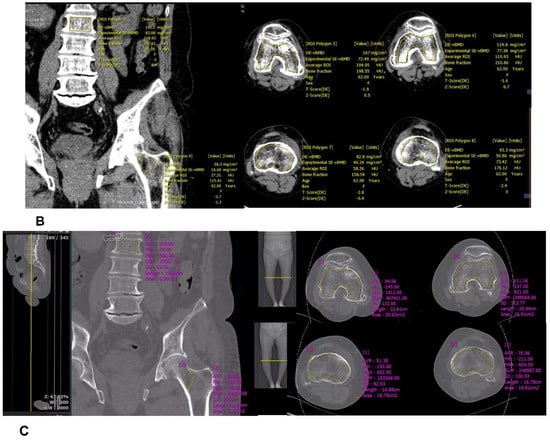

Figure 2.

(A) Assessment of dual x-ray absorptiometry (DXA) in the lumbar spine and femur neck; (B) Manual definition of the region of interest (ROI) and assessment of bone mineral density (BMD) derived from dual-energy computed tomography (DECT) in the distal femur and proximal tibia using dedicated DECT postprocessing software; (C) Manual definition of the region of interest (ROI) and assessment of Hounsfield unit (HU) derived from dual-energy computed tomography (DECT) in the distal femur and proximal tibia using dedicated DECT postprocessing software.

Phantomless volumetric BMD assessment of L2 and the left femur neck with DECT requires manual delineation of trabecular volumes of interest (VOI) in the L2 vertebra and the left pelvis, which was carried out by one of the authors with dedicated software (Examine, Siemens Healthcare, Erlangen, Germany). Regions of interest (ROIs) defined to best include trabecular bone and exclude any cortical bone were also drawn manually on the images loaded into the software (Figure 2B). The software then performed calculations according to a dedicated algorithm and the resulting output included the volumetric BMD values.

For DECT HU analysis, one of the authors, working at a conventional PACS workstation, manually defined polygonal ROIs on standard bone reconstructions in sagittal or axial image series (Figure 2C). The ROIs were positioned in the anterior trabecular bone space of the L2 vertebral body, as proposed by several studies [,,]. Thereby, the reader was instructed to avoid attenuation heterogeneity by placing the ROIs in areas of spinal hemangiomas or other causes of attenuation heterogeneity. All HU values were obtained as averages of three serial polygonal ROIs.